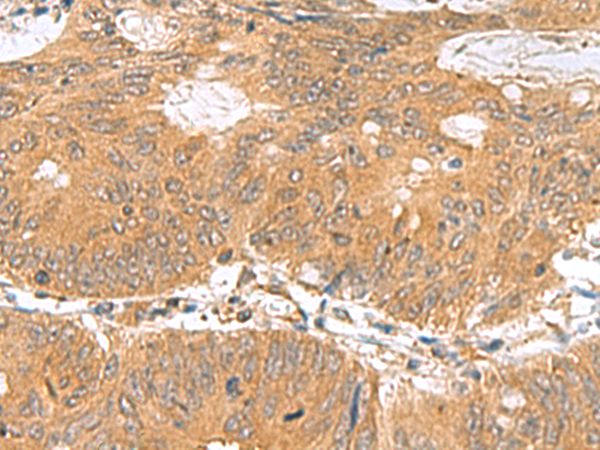

The image is immunohistochemistry of paraffin-embedded Human liver cancer tissue using 47433(GEMIN7 Antibody) at dilution 1/70.(Original magnification: 200)

The image is immunohistochemistry of paraffin-embedded Human colorectal cancer tissue using 47433(GEMIN7 Antibody) at dilution 1/70.(Original magnification: 200)